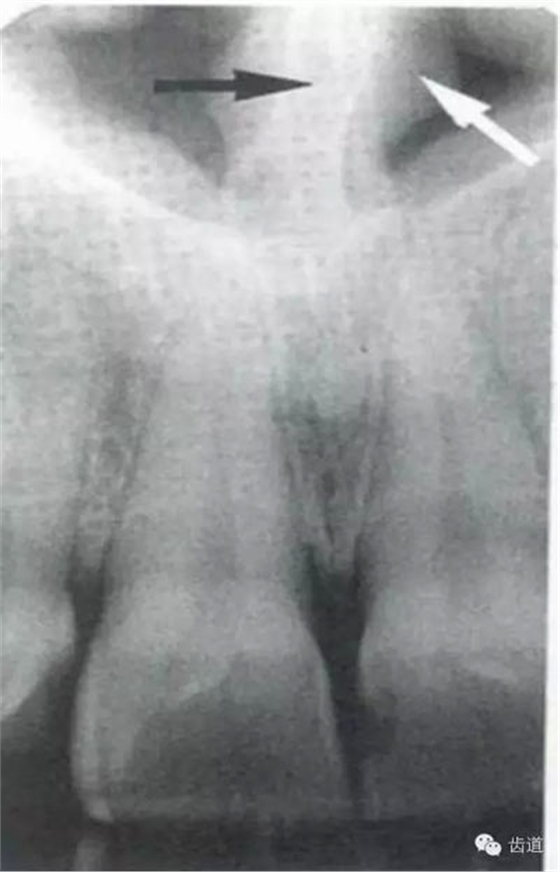

牙頸部Burnout征象:有時(shí)因投照技術(shù)問(wèn)題而造成牙頸部近中或遠(yuǎn)中呈低密度影像,位于牙釉質(zhì)和牙槽嵴頂之間。